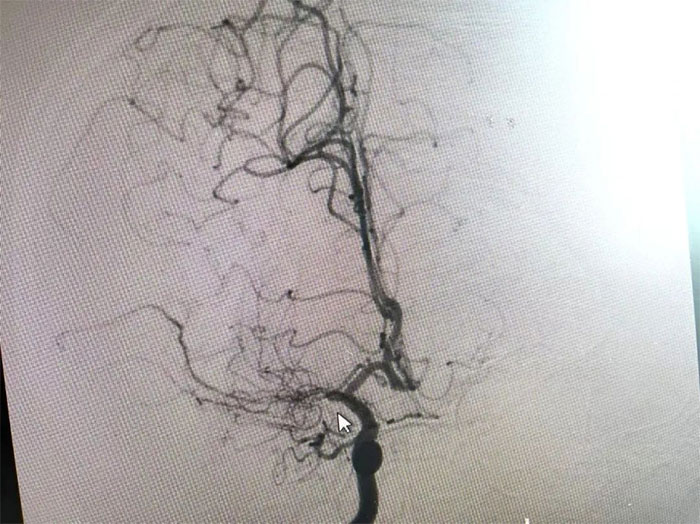

在与患者及家属充分沟通后,李振并主任为周先生展开了DSA(数字减影血管造影)检查。

在检查中发现,周先生右侧大脑中动脉M1段闭塞,可见烟雾状异常血管网生成;左侧大脑中动脉M1段重度狭窄(约70%)。符合烟雾病的典型影像学特征。

▲ 检查发现烟雾状异常血管网